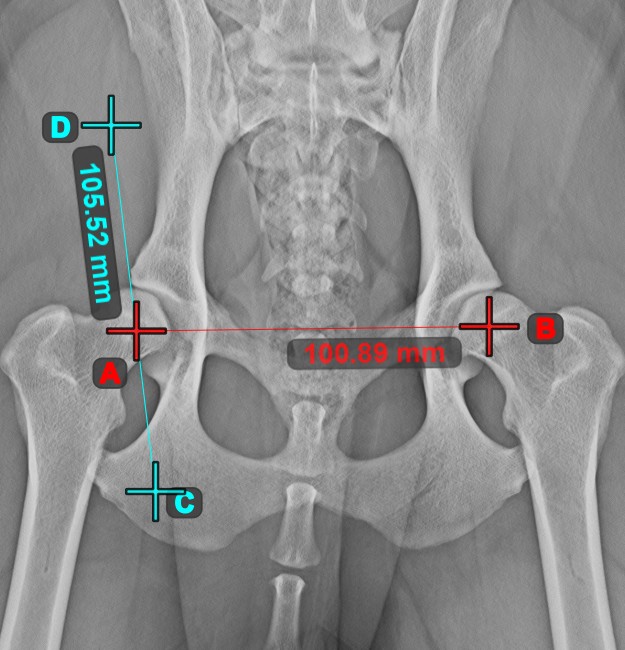

Line Measurement¶

Select the Line Measurement tool and assign it to one of the available mouse buttons. Place the start and end points on the scene or select them from already existing points on the image. The distance between the two points will be automatically

calculated by using the default calibration data, or the recalibrated data by the length calibration measurement.

Modify the start and end point by using the Select/Move Item tool. The distance between the two points will be automatically recalculated.